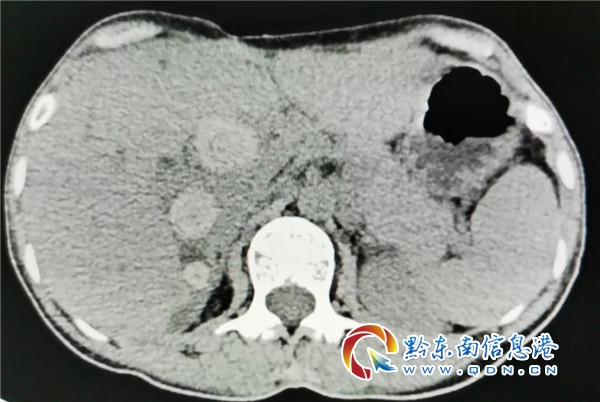

因为求生与信任,因为仁心与大爱,医院与患者紧紧地拥抱在一起,面对病魔,他们共同努力,共克时坚。为弄清李奶永病情病史,住院当天,该院专家杨思清随即安排医务人员立即做好辅差,通过磁共振、CT检查,发现其肝内胆管多发结石伴肝内胆管扩张;胆总管中上段结石并胆总管扩张;胆囊术后缺如。

同时,为做到精准再精准,根据李奶永的辅察结果,外二科主任医师杨思清,再次组织科室专家进一步会诊,对患者病情进行再次系统性分析研判 ,最后诊断患者为急性梗阻性胆管炎;胆总管结石;肝内胆管结石;胆肠吻合术后;胆源性胰腺炎;胃炎。